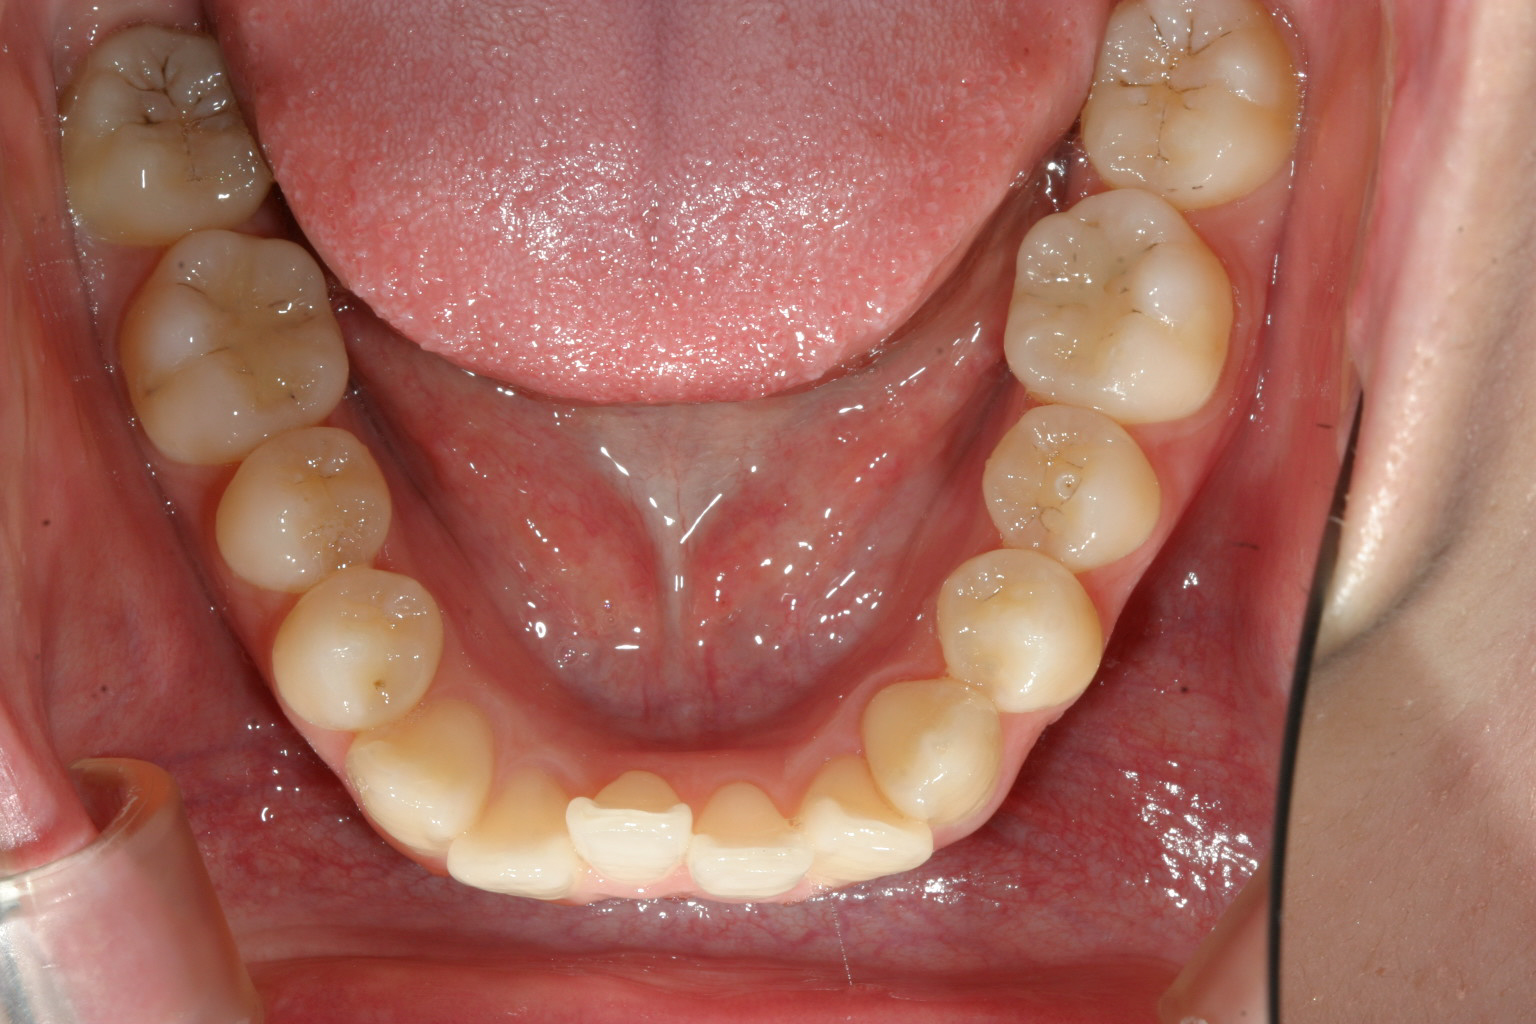

下顎もU字に変えて配列しています。

今回のケースは上下のアーチフォームがV字になっていた為前歯が上手く並ばず

ガタガタしていました。

全体的なアーチフォームをU字に改善するだけで問題は改善します。

この様な処置はインビザライン治療では得意な処置です。